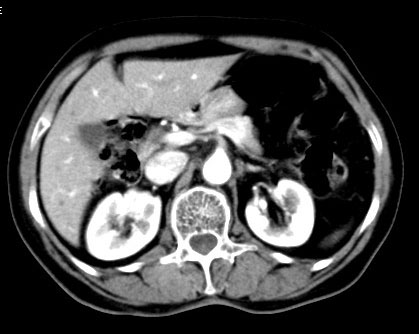

以下是增强:

怎么没有动脉期的图像,平扫密度较高,静脉期环形强化,壁光整,高密度囊肿?肾癌?

囊性肾癌伴下腔静脉癌栓形成。(强化后见主动脉明显强化,下腔静脉左后缘显影,管腔内见低密度癌栓形成。)

右肾囊性肿块影,不稍厚有强化,囊内低密度与胆囊相对比稍高。考虑囊肿并感染,或者脓肿。